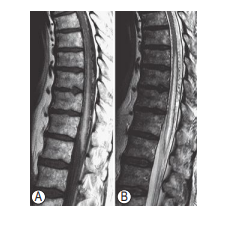

A 35-year-old with Osler-Weber-Rendu syndrome presents with gait disturbance. T2W MRI is shown below. Which one of the following is most likely?

e. Type IV-C perimedullary (ventral intradural) AVF

Perimedullary (ventralintradural)AVFs have a fistulous connection which is intradural but

extramedullary,with feeding vessel(s) from the anterior spinal artery. Venous drainage is via an enlarged

coronal venous plexus. These lesions may present in

young adults, but presentation in the third to sixth

decade is more likely. SAH is possible with subsequent acute neurologic deterioration, but a gradual

progressive neurologic deterioration is common.

Three subcategories of intradural spinal AV fistulas

have been recognized, with different treatment

options appropriate for each.

* Type IVa has a single feeding vessel, often

the artery of Adamkiewicz, with low flow

through the arteriovenous shunt and moderate venous enlargement. Endovascular

techniques are difficult with these lesions

due to the small size of feeding vessels

hence surgical excision is often mandated.

* Type IVb AV fistulas are medium-sized, often

with multiple feeding vessels, and more

marked venous enlargement. Embolization in

these lesions is easier, due to the increased size

of feeding vessels. In cases of incomplete shunt

obliteration with an endovascular approach,

direct surgical excision may be necessary.

* Type IVc are giant, multipediculated, highflow fistulas with large, tortuous draining

veins. Spinal ischemia may develop in these

lesions secondary to vascular steal. Due to

the size of these lesions, surgery is technically difficult and may jeopardize

the spinal cord. Treatment is hence

through combination of endovascular ablation, followed by surgical excision of

retained elements.